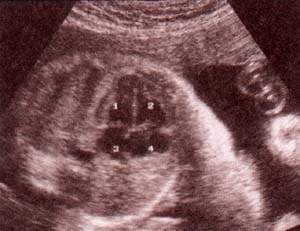

| fig 29.– (a). corazón corte 4 cámaras. proyección apical. 32 semanas. ventrículo izquierdo (1). ventrículo derecho (2). aurícula izquierda (3). aurícula derecha (4). | fig. 29. – (b). proyección subcostal. 36 semanas. ventrículo izquierdo (1). ventrículo derecho (2). aurícula izquierda (3). aurícula derecha (4). |